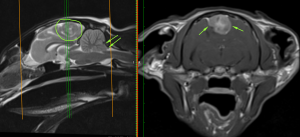

Violet has a very dedicated owner and she wanted to do everything she could. She agreed to a surgical approach to Violet’s treatment plan. The next step was to undertake an MRI scan for surgical planning. MRIs can provide a much more detailed picture of the central nervous system. The MRI scan confirmed a mass in the midline of the cerebrum. Given the appearance and location, this was highly likely a tumour known as a meningioma. This is a tumour of the meninges (the outer membranes of the brain).

Meningiomas are the most common brain tumour found in cats and are generally benign, having a tendency to cause local compression as they grow, rather than spreading to other parts of the body. In Violet’s case, as her brain tumour grew, she started to show clinical signs, affecting her neurological function. This is because there is a limited amount of space within the skull and when the tumour grows it compresses surrounding brain tissue. With Violet, the tumour had grown to such a size that her cerebellum had herniated through the back of her skull (arrows).